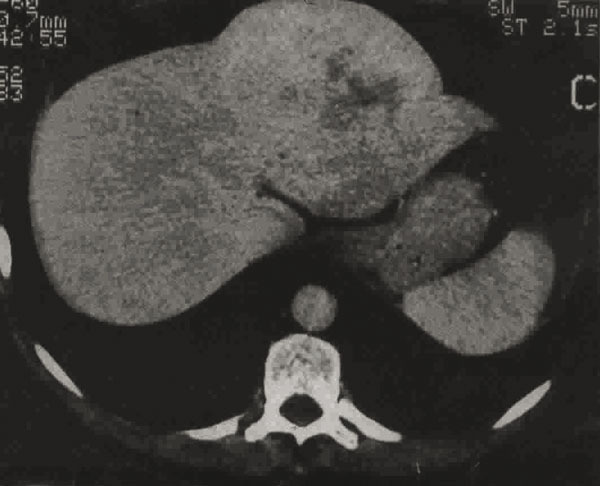

La Revue du Praticien - Jacques Belghiti Lésion hypervasculaire encapsulée, sans cicatrice centrale. L’hypodensité centrale est la conséquence d’un remaniement nécrotique. Cette tumeur est difficile à distinguer du carcinome fibrolamellaire.